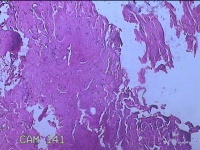

性别

男

年龄

27岁

临床诊断

皮下结节

一般病史

发现下颌部结节1·个月余,伴局部隐痛不适。

标本名称

下颌部结节

大体所见

灰白暗红色结节0.8x0.5x0.2cm一个,表面糜烂。